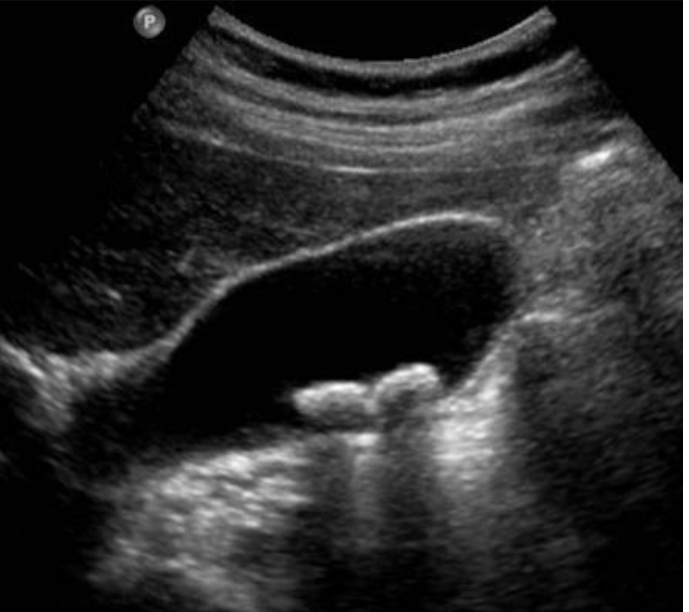

Abdominal Ultrasound most accurate if fasting >8 hrs, as stones are best seen in a distended GB filled with bile

Stones cast shadow + move around

Cholelithiasis